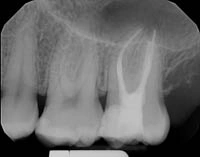

Before and After